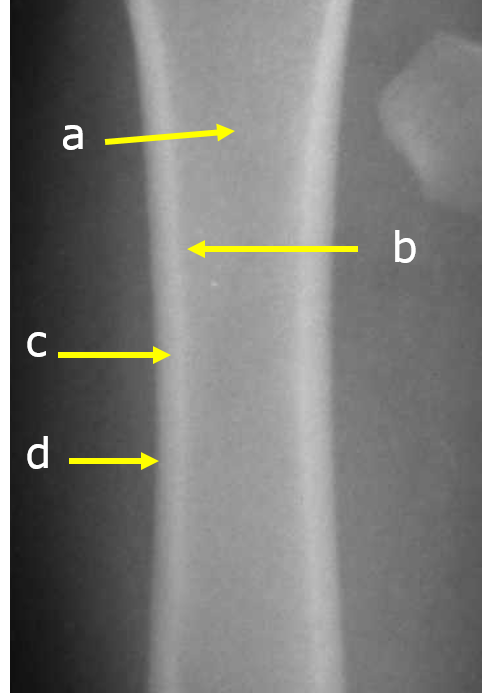

Label

a. Medullary cavity

b. Endosteum of cortex

c. Cortex

d. Periosteum surface